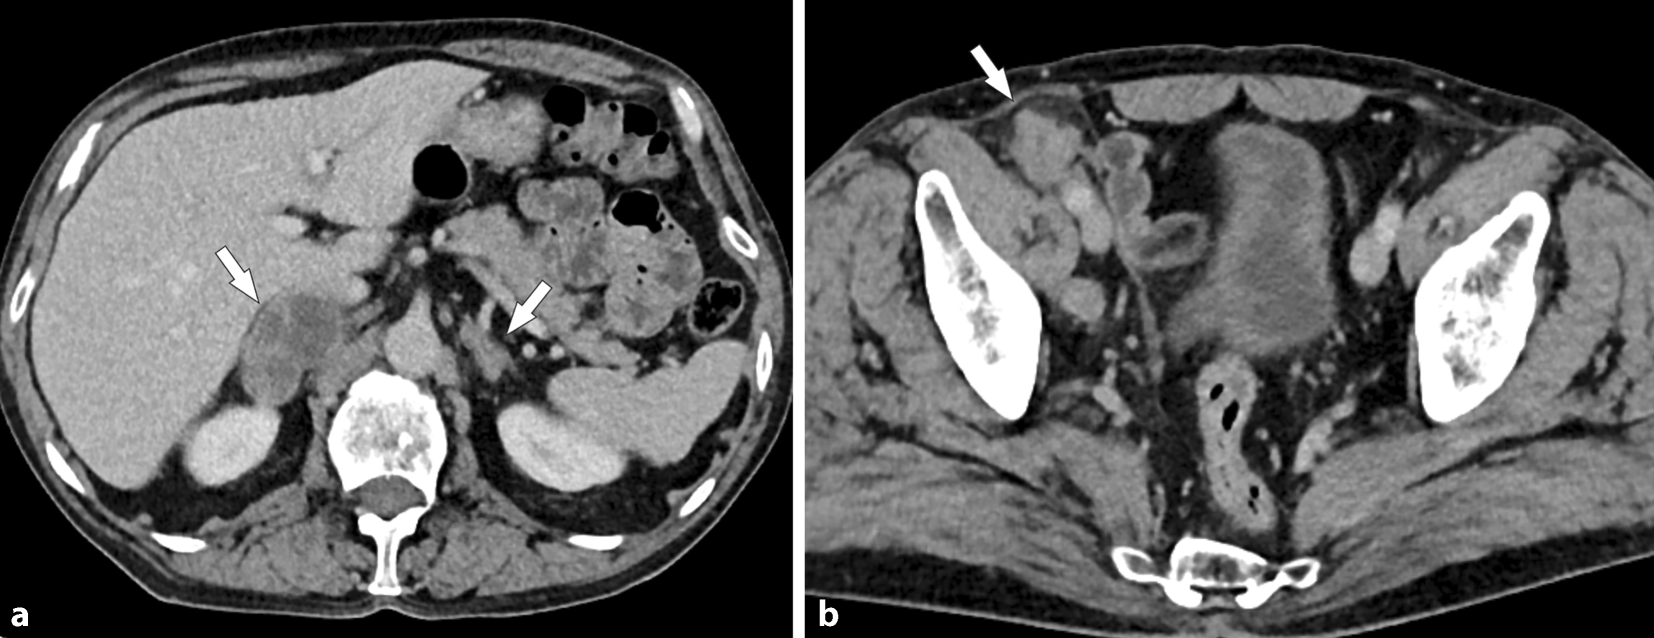

Abb. 1

Die Kontrastmittel-verstärkte MDCT zeigt a bilaterale, zum Teil zystische Nebennierenraumforderungen (Pfeile) und b suspekt vergrößerte Lymphknoten rechts parailiakal (Pfeil)